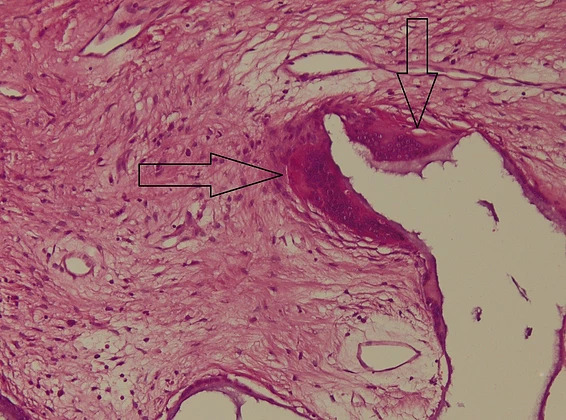

The histolopathological analysis performed shows in the meshes of the prosthetic material, fibrovascular tissue and minimal polymorphic inflammatory infiltrate (lymphocytes, plasma cells and polymorphonuclear neutrophils) and moderately frequent multinucleated giant cells of the “foreign body” type at the interface with the hydroxyapatite as well as osteoclasts at the interface with the hydroxyapatite nanocomposite material. At different levels in the muscle tissue and in the corresponding sclera, amorphous, acellular material (mono and multifilament surgical threads) bordered by multinucleated giant cells of the “foreign body” type is observed. (Figure 11,12). It can be observed that the invasion of the implant with fibrovascular material begins from the incision and the initial suture area, and the presence of multinucleated giant cells of the foreign body type in not very large numbers attests to good compatibility, at least equal to that of the suture material.

Figure 12: Histopathological appearance of the hydroxyapatite implant in hematoxylin-eosin (HE) staining – subject 2. Marked with arrows are the osteoclasts at the interface with the nanostructured hydroxyapatite material. The presence of osteoclasts attests to the tendency of hydroxyapatite degradation necessary for the formation of new bone tissue.